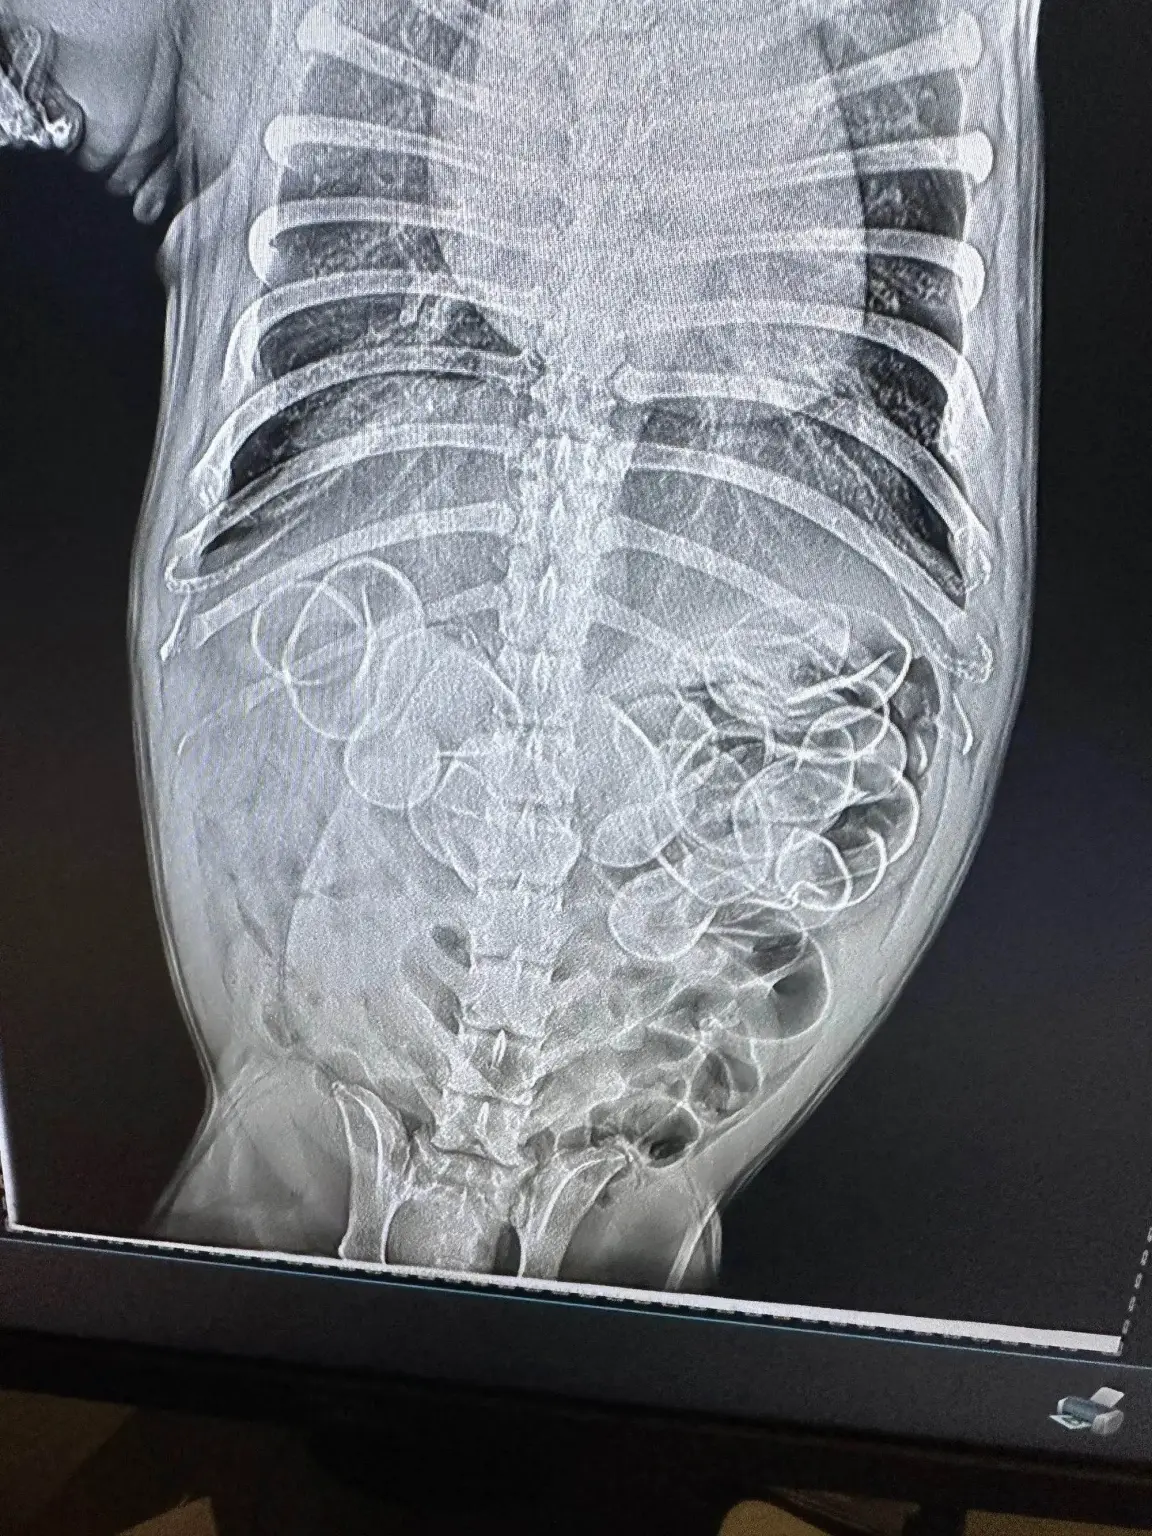

Având dubii că animalul ei de companie ar putea fi vinovat de dispariția raței, l-a dus imediat la veterinar. A fost șocată când medicii au realizat o radiografie a stomacului câinelui, localizând cel puțin cinci dintre jucării în imagine.

Bulldog-ul francez a fost dus de urgență în sala de operații, acolo unde veterinarii au reușit să scoată în plus șase rațe- 11 în total. Ingerarea cauciucului poate fi extrem de periculoasă pentru câini, fie că este vorba de rațe de cauciuc precum acest biet cățeluș sau de o simplă jucărie de cauciuc de la magazinul de animale, notează Pet Educate.